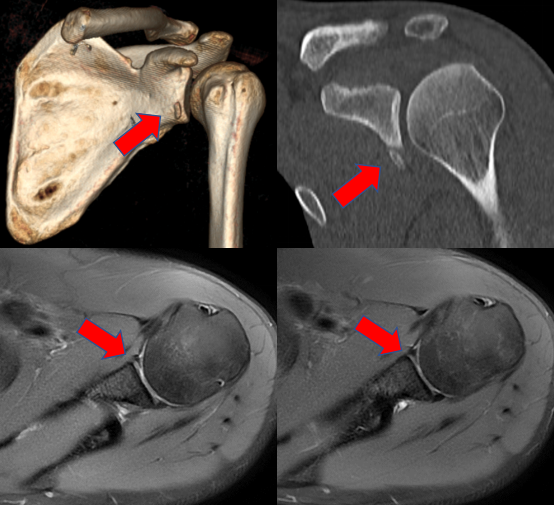

影像学提示患者肩关节盂唇损伤,可见明显的骨片影,盂唇与关节盂分离

术中镜下图片:损伤撕裂的盂唇清晰可见,术后(右)已成功修补